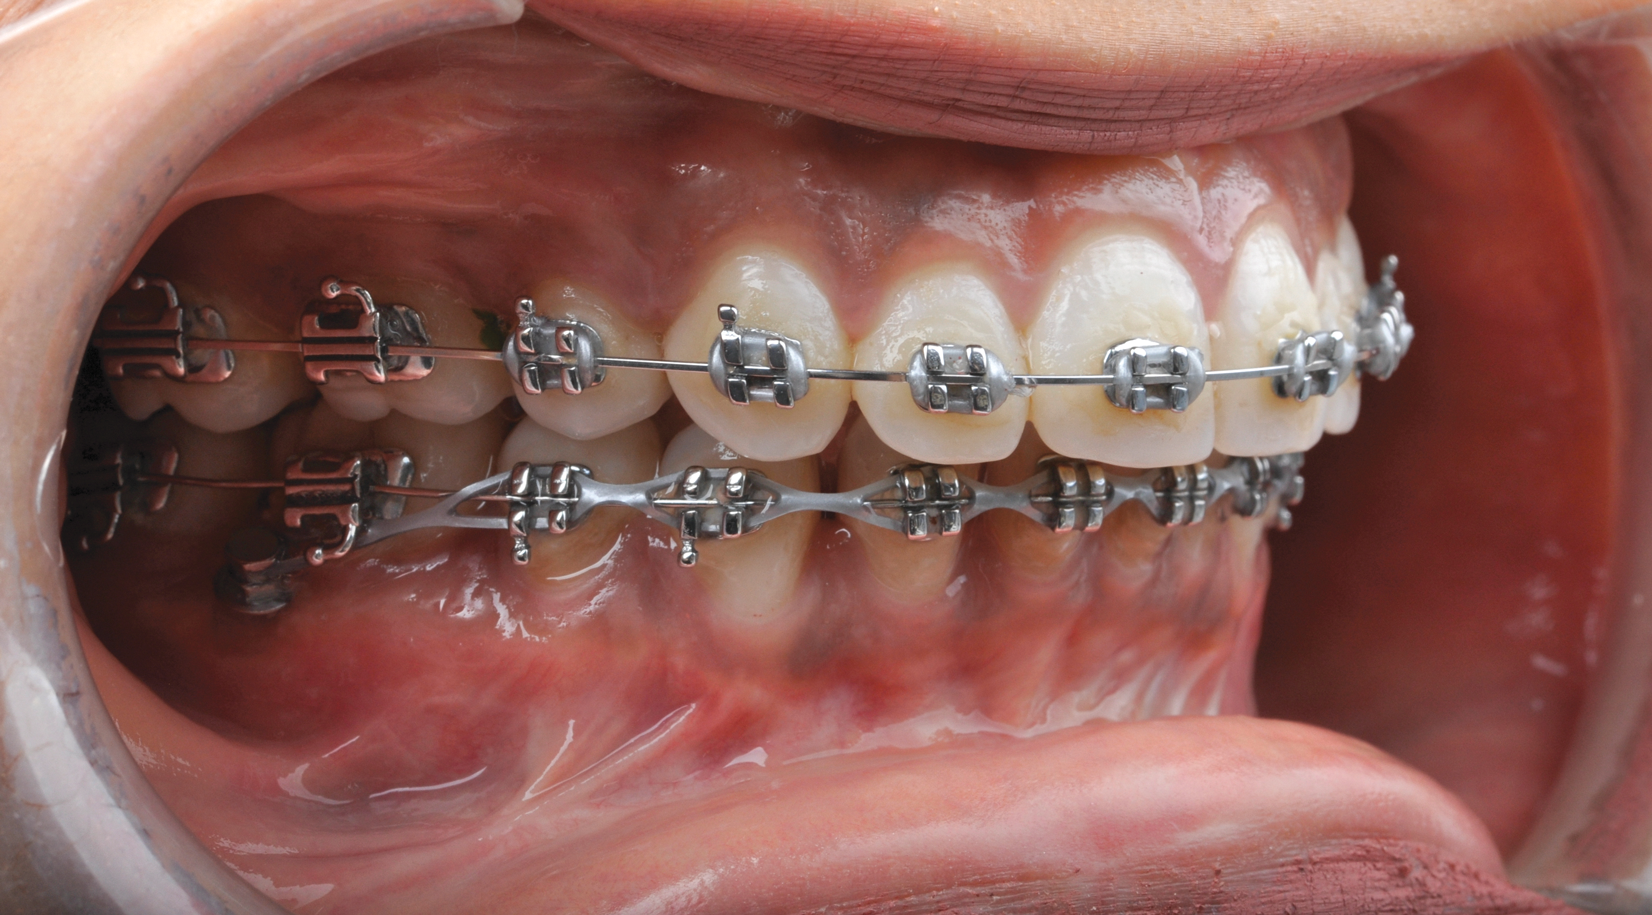

Fig 18. Bite interdigitation to finalize surgical orthodontic correction. After orthodontics, periodontal plastic surgery, bleaching, microabrasion, and restorative dentistry were performed.

Figure 18

Fig 19. Bite interdigitation to finalize surgical orthodontic correction. After orthodontics, periodontal plastic surgery, bleaching, microabrasion, and restorative dentistry were performed.

Figure 19

Fig 20. Bite interdigitation to finalize surgical orthodontic correction. After orthodontics, periodontal plastic surgery, bleaching, microabrasion, and restorative dentistry were performed.

Figure 20